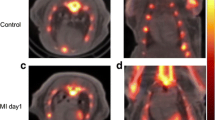

Representative micro-PET–CT images of [18F]FEDAC uptake in MI model rats are shown in Fig. 4. PET images revealed a remarkable defect area at the ischemic myocardium in the anterior wall and the vertex cordis (Fig. 4). Signals from the blood pool in the heart chambers were minimal. The maximal normal-to-ischemic uptake ratios in the MI model were 10.47 ± 3.03 and 3.92 ± 1.12 (P = 0.025) at 1.5 min and 27.5 min, respectively (Fig. 5). Over the same period, the heart to liver ratio remained relatively ideal and stable (from 2.03 ± 0.42 to 2.24 ± 0.29 (P = 0.517), with no significant change over time. There were no adverse effects associated with the injected radiopharmaceutical.

Following PET evaluation, we visualized decreased levels of TSPO expression in the ischemic myocardium in rats using [18F]FEDAC. Surgery resulted in ischemic injury to the anterior wall and vertex cordis in the heart. Frozen sections of myocardial tissue revealed ischemic foci on the anterior wall of the left ventricle, consistent with the imaging sites (Fig. 6A). TTC staining showed MI damage in the same area of the anterior wall of the left ventricle (Fig. 6B). The in vitro autoradiography results are shown in Fig. 6C. [18F]FEDAC binding was lower in the injured compared with the normal area.

[18F]FEDAC in a myocardial injury rat model. A Frozen sections of myocardial tissue showing ischemic injury foci on the anterior wall of the left ventricle, consistent with the imaging sites. B TTC staining showing myocardial ischemia in the same area of the anterior wall of the left ventricle. C In vitro autoradiography results showing lower 18F-ligand binding in the injured compared with the normal area

[18F]FEDAC PET–CT revealed that TSPO expression was pathologically decreased in ischemic myocardium compared with normal cardiac tissue. Differences in TSPO expression in the MI model could be detected and quantified with [18F]FEDAC PET–CT, with normal-to-ischemic uptake ratios from 10.47 ± 3.03 (1.5 min) to 3.92 ± 1.12 (27.5 min) (P = 0.025), enabling the non-invasive imaging of myocardial injury in the acute phase as early as 30 min after injection. In vitro autoradiography further supported the specific binding of [18F]FEDAC to TSPO in MI cardiac sections.